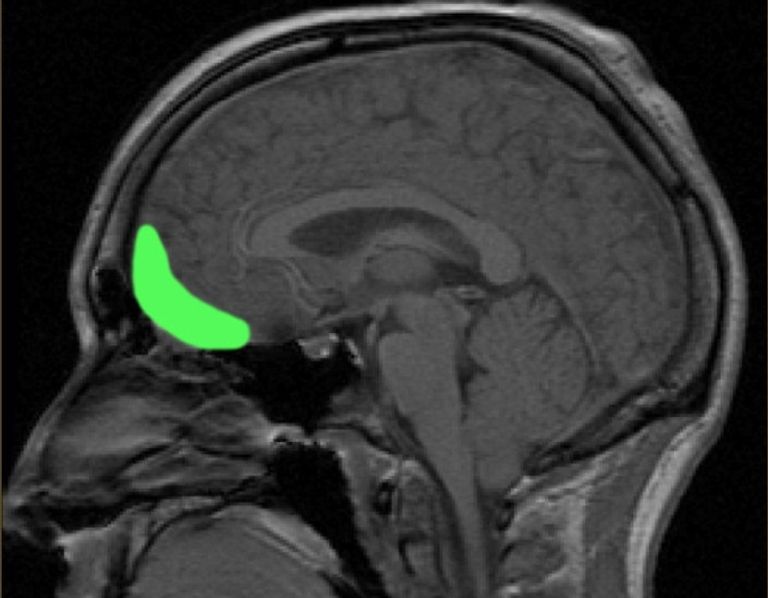

مصطلح "ويتزلزوخت" (مزيج من الكلمتين الألمانيتين "نكتة" و"إدمان") ظهر لأول مرة في عام 1890 على يد طبيب الأعصاب الألماني هيرمان أوبنهايم، الذي لاحظ أن تلف الفص الأمامي الأيمن من الدماغ، سواء كان نتيجة لإصابة أو مرض، يؤدي أحياناً إلى سلوك مزاح مفرط لدى المرضى.

واليوم، يدرك العلماء أن "ويتزلزوخت" يمكن أن يتداخل مع مجموعة أخرى من الأعراض العصبية تعرف باسم "الموريا" (Moria)، والتي تتميز بالبهجة المرضية، وكلا التغيرين السلوكيين مرتبطان بتلف في الدائرة الجبهية المدارية، المسؤولة عن اتخاذ القرارات، والتي يمكن أن تؤدي إلى سلوك غير مدروس عند تعرضها للتلف.